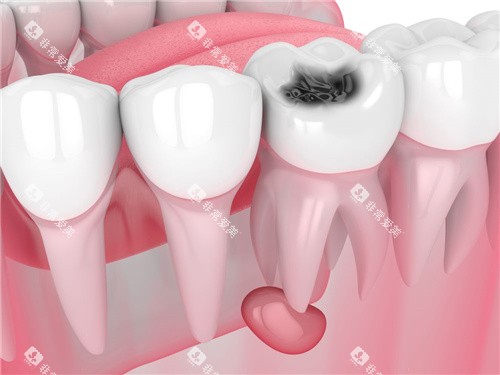

德恒口腔专注于口腔疾病的治疗和预防。

在牙周病治疗方面,德恒口腔有着独特的治疗方法。

医生们会根据患者的病情制定个性化的治疗方案,采用综合治疗的方法,包括洁治、刮治、药物治疗等,有效地控制牙周病的发展。

在牙齿美容方面,德恒口腔能够为患者提供牙齿贴面、冷光美白等多种美容项目,让患者拥有洁白亮丽的牙齿。